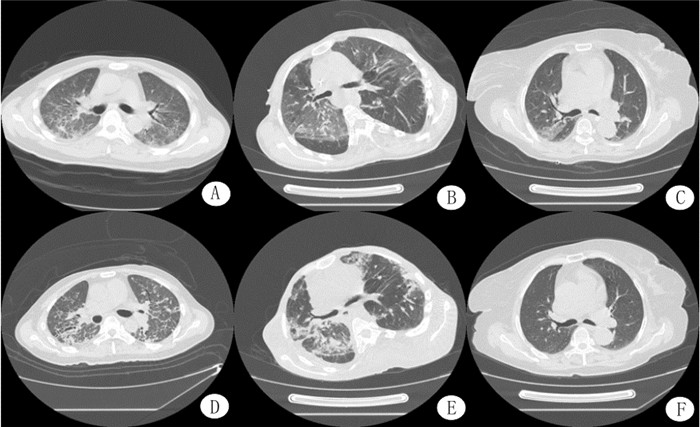

3组患者入院时肺部CT特征比较差异无统计学意义;治疗后7 d,C组患者肺部CT表现以磨玻璃样改变为主,其比例高于A、B组,而A、B组大多数患者已出现肺实质病变及肺间质病变,其比例均高于C组,且A组高于B组,各组间比较差异有统计学意义[A组:56.7%(17/30)、B组:29.41%(10/34)、C组:10.0%(4/40),χ2=17.84, P<0.01];入院14 d,C组患者两侧肺野出现小片状渗出性改变和胸膜下的不规则线影,A、B组见肺间质变影,范围较大可见支气管影像,其比例均高于C组,且A组高于B组,各组间比较差异有统计学意义[A组:61.1%(11/18)、B组:26.09%(6/23)、C组:6.06%(2/33),χ2=18.49, P<0.01]。见图 1。

| A:血液灌流组治疗7 d的肺部CT表现;B:大黄为主中药组方联合血液灌流组治疗7 d的肺部CT表现;C:大黄为主中药组方联合持续血液灌流组治疗7 d的肺部CT表现;D:血液灌流组治疗14 d的肺部CT表现;E:大黄为主中药组方联合血液灌流组治疗14 d的肺部CT表现;F:大黄为主中药组方联合持续血液灌流组治疗14 d的肺部CT表现 图 1 3组患者治疗后肺部CT的比较 Figure 1 The comparison of the histopathological changes in lung CT after treatment among three groups |

血液灌流(HP)是目前清除血液循环中毒物的常用方法,它是通过灌流器中活性炭、树脂及氧化淀粉等广泛吸附效应的物质来清除已被吸收入血的毒物或药物,对毒物具有非选择性的吸附作用,对小分子和中分子的毒物吸附效果明显。百草枯是中分子物质,在百草枯中毒早期(2~4 h内)应用者效果较好,HP是患者早期,特别是刚入院时应用最广泛最主要的血液净化方式,HP治疗开始越早患者病死率越低[6]。在HP过程中,通过监测活化部分凝血活酶时间(APTT)来调整肝素的用量,确保APTT维持在正常上限的1.5~2.0倍,故在此基础上,能维持所有患者机体处于相对同等的抗凝和促凝内环境,因此持续血液灌流和间断血液灌流对机体出血的影响以及凝血和血小板计数的影响差异无统计学意义。PⅢP是Ⅲ型前胶原转化成Ⅲ型胶原时释放的多肽,在纤维化早期即升高,是目前评价早期肺纤维化的一个重要指标[4],肺部CT则能更加直观地观察APP患者肺损伤的演变,随着时间的变化呈现出由磨玻璃影或实变逐渐到纤维化,即肺渗出-实变-纤维化的过程。序贯器官功能衰竭评分(SOFA)在临床上常用于评价脏器功能衰竭的严重程度,目前主要对呼吸、凝血、肝脏、循环、神经等五个系统评价,因此,在重症患者中得到了广泛应用[13],因此本研究选择PⅢP联合肺部CT变化和SOFA评分来评估APP患者的病情变化及肺损伤的程度。结果显示,治疗后3、7、10、14 d,3组患者PⅢP水平逐渐升高,大黄为主中药组方联合持续血液灌流组升高缓慢。APP患者血中PⅢP水平与百草枯浓度呈正相关;在患者治疗过程中SOFA评分则呈现先升高后降低的变化,C组先升高缓慢后降低显著(P<0.05);肺部CT显示治疗后7 d,C组患者表现以磨玻璃样改变为主,其比例高于A、B组,而A、B组大多数患者已出现肺间质病变,其比例均高于C组,且A组高于B组,各组间比较差异有统计学意义。